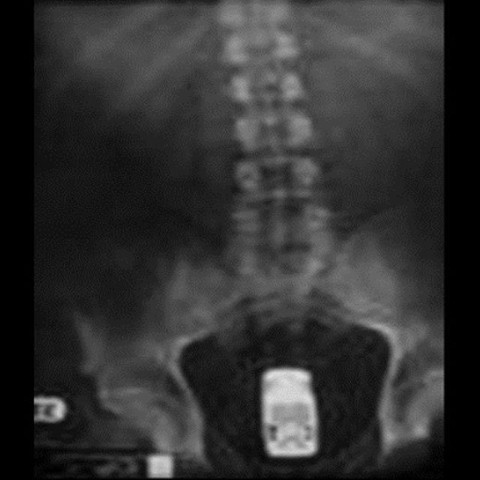

Galerinin tamamı için tıklayınızOYUNCAK ARABA; Jackass adlı televizyon şovunu hazırlayan isimlerden olan Ryan Dunn acil servis doktorlarının tepkisini ölçmek için rektumuna oyuncak araba sokmuştu.